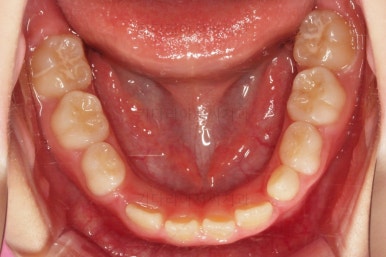

치료 22개월 째 종료시점의 사진입니다.

전후 비교해 볼게요.

교합도 좋아졌고 앞니 관계(반대교합, 개방교합)도 개선이 잘 되었어요.